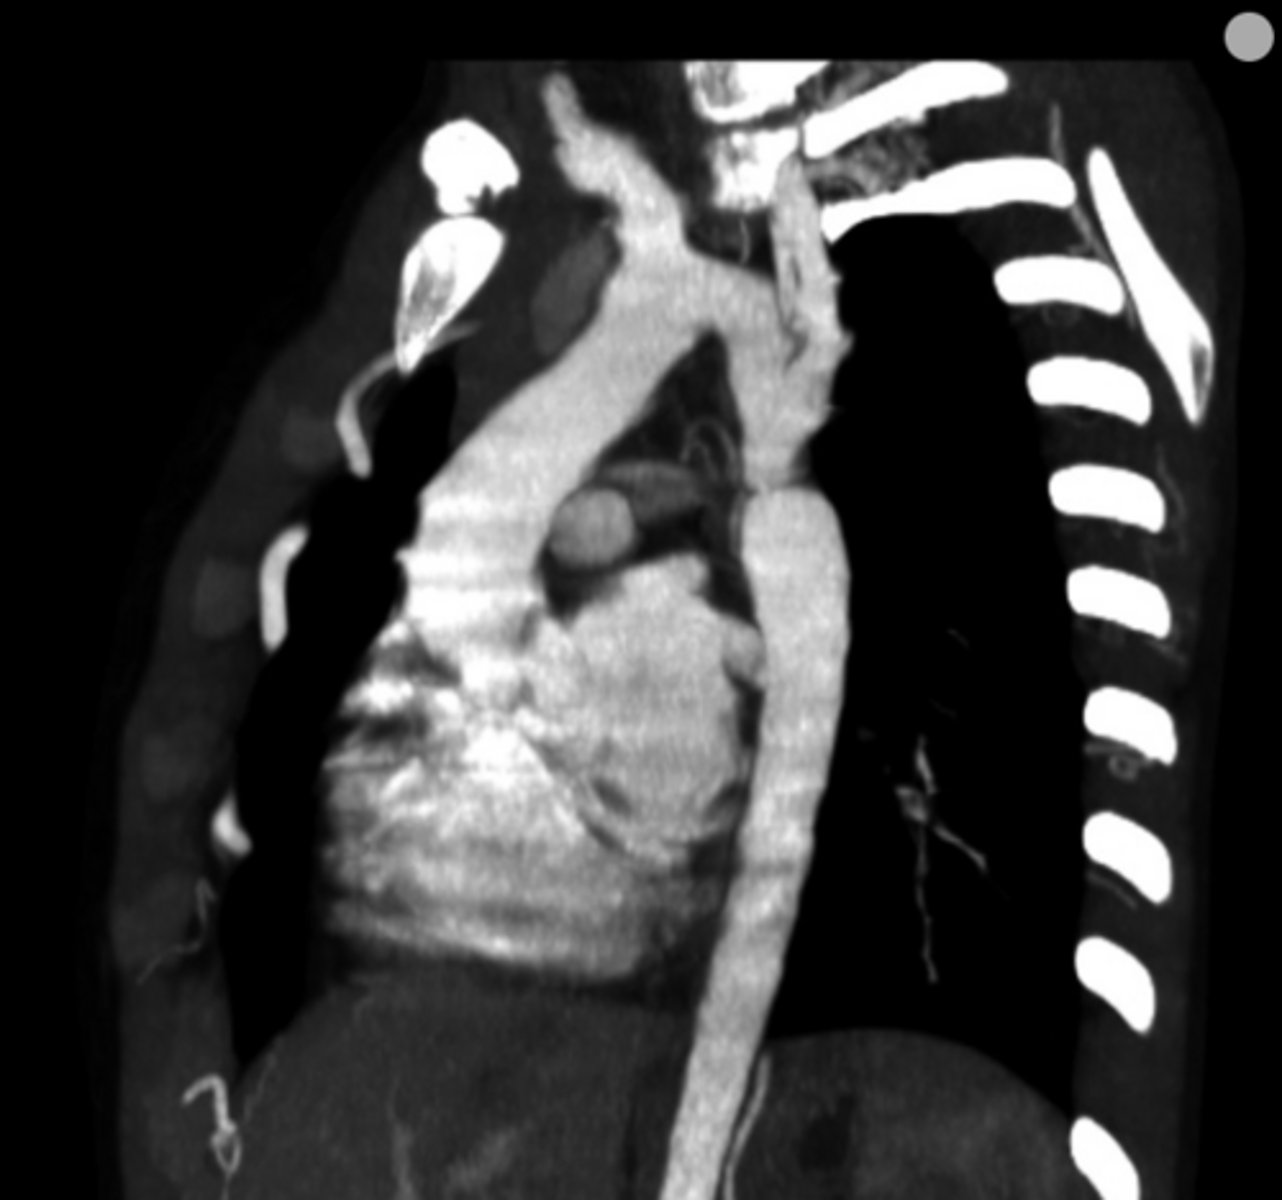

What is coarctation of the aorta?

Congenital narrowing of the aorta.

What are the key features of infantile coarctation of the aorta?

Symptomatic in early childhood, tubular hypoplasia of the aortic arch, occurs proximal to a PDA.

What are the key features of adult coarctation of the aorta?

Narrowing opposite a closed ductus arteriosus, distal to the great vessels from the aortic arch.

What is the chest radiograph finding in coarctation of the aorta?

Figure 3 sign.